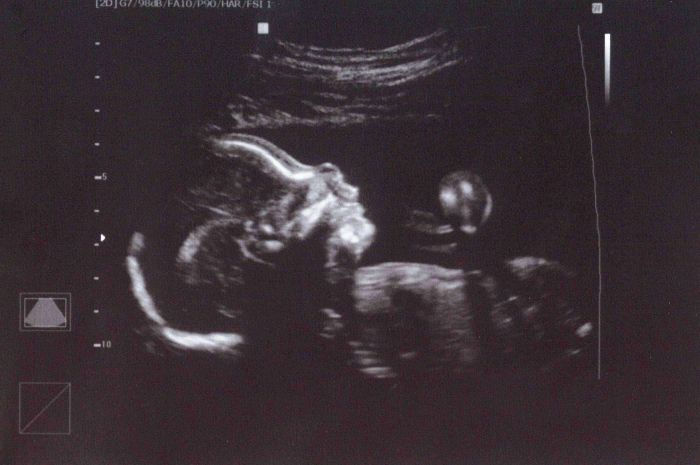

ahoj holky, tak jsme dnes byli na utz a všechno v naprostém pořádku - máme velikou radost! a v pátek se našem Béďovi narodili bratránek a sestřenka, takže se rodinka pomalu a jistě rozrůstá. posílám dnešní fotečku - taky ušlechtilý profil, jak to ty naše mimča dělají?:)

Neužila jsem si tolik jako na screeningu v I. trimestru. Za prvé jsme tam hodinu a půl čekali než jsme šli na řadu, což nás poměrně otrávilo a následně i přístup paní Dr. Působila dost nejistě při každém měření atd... až jsem se vždycky ohlídla na přítele a ten na mě kývnul, ať jsem v klidu. Holky, byla jsem konsternovaná tak, že jsem si neřekla ani o fotku ani jsem se nezeptala, jestli je v bříšku opravdu chlapeček. Hlavně, že je v pořádku! Spinkal a tak mi do bříška stále žďuchala, aby teda ukázal, že i na druhé ručičce má pět prstíků, na několikátý pokus se to povedlo :-) Jaký měl výraz, no přišlo mi, že si něco povídá a má roztomilou malou pusinku a nosánek trochu nahoru ;-) Jukněte alespoň na fotku z 16. tt, kde mi bylo řečeno, že je to chlapeček.